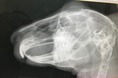

奥歯も問題なし。